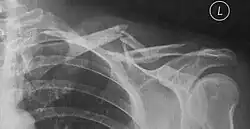

Häufig ergibt sich schon bei der klinischen Untersuchung die Diagnose durch lokale Schwellung, Druckschmerz, tastbare Knochenenden unter der Haut oder Knochenreiben (Krepitation). Die Diagnose wird durch eine Röntgenuntersuchung bestätigt.

Klavikulafraktur, Claviculafraktur oder Schlüsselbeinbruch ist ein Knochenbruch (Fraktur) des Schlüsselbeines (lateinisch clavicula) und bei Erwachsenen nach dem Bruch der Speiche die zweithäufigste Fraktur.[1] Ursache ist meist ein Sturz auf die Schulter, seltener auf den ausgestreckten Arm, oder eine, oft nur geringe, unmittelbare Gewalteinwirkung auf das Schlüsselbein. Seltene Komplikationen sind Gefäß- oder Nervenverletzungen.